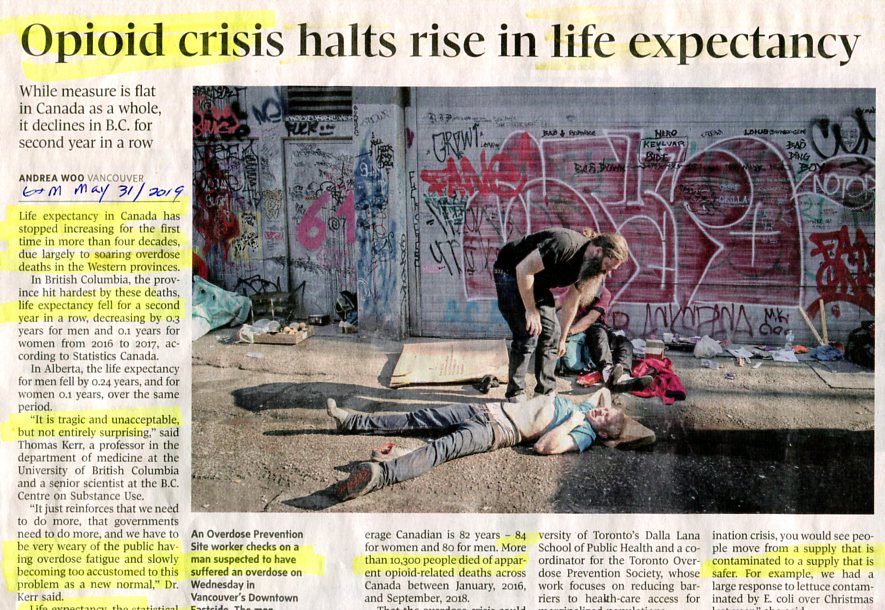

(tireless advocate for THC harm reduction from opioids)

Canada Press, June 19, 2024

ORWELLIAN WAR BY DRUGS